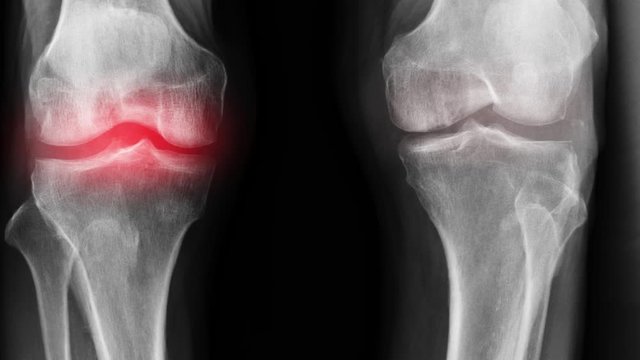

Femme de 54 ans. Son articulation est entièrement restaurée. La durée du traitement : 14 jours :

Traitement de l'articulation de la hanche d'un patient âgé de 44 ans. La douleur atroce qui a torturé le patient pendant 2 ans, a été complètement guérie :

Restauration de l'articulation du coude. Patiente, 31 ans. Durée du traitement par la Voralis Сonfort : 12 jours. Son articulation est entièrement restaurée :